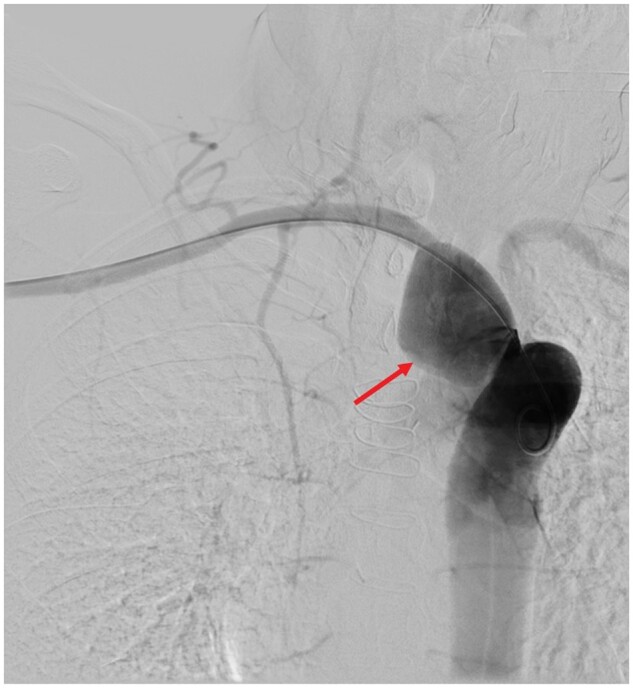

Aneurysms of an aberrant right subclavian artery (ARSA) are rare but constitute a potentially lethal condition, especially with concomitant Marfan syndrome (MFS). A 27-year-old female with confirmed MFS presented with a relevant progression of a known aneurysm of an ARSA in MRI. The patient had undergone valve-sparing aortic root replacement (David procedure) 4 months prior. After interdisciplinary discussion, she underwent endovascular exclusion of the aneurysm using a combination of established vascular plugs and novel shape memory polymer embolization plugs to fill the large ARSA aneurysm volume. The shape memory polymer embolization plugs expand in the vessel to a porous scaffold, designed to support thrombus formation throughout its structure. The polymer is also radiolucent, which minimizes artefact and facilitates follow-up imaging. Development of a strategy for the treatment of ARSA aneurysms is challenging and different surgical, endovascular, and combined approaches have been published. Interdisciplinary discussion is crucial to minimize the overall risk and trauma. In our case of a young female and new mother, an endovascular approach was successfully and safely performed. The future need for surgery due to concomitant MFS is expected.